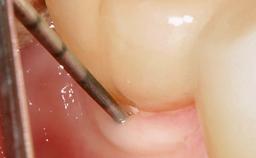

Surgical Management of Peri-Implantitis: Removal of Implant Due to Recurrent Infection Using an Implant-Retrieval Tool

Despite anti-infective surgical treatment, some patients may experience recurrent infection and progressive bone loss requiring additional treatment. This case describes a conservative approach using an implant retrieval tool without the need for excessive bone removal or use of a trephine.

A 65-year-old female patient was referred to the periodontist for assessment and management of infection associated with an implant at site 12. The general dentist had noted suppuration on probing during examination.